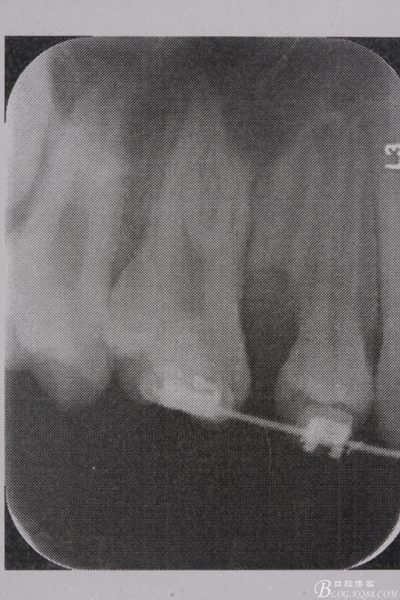

圖4. 加拍局部根尖片,15牙根顯露無疑,遂考慮拔除15,才能關閉16與14之間的間隙。